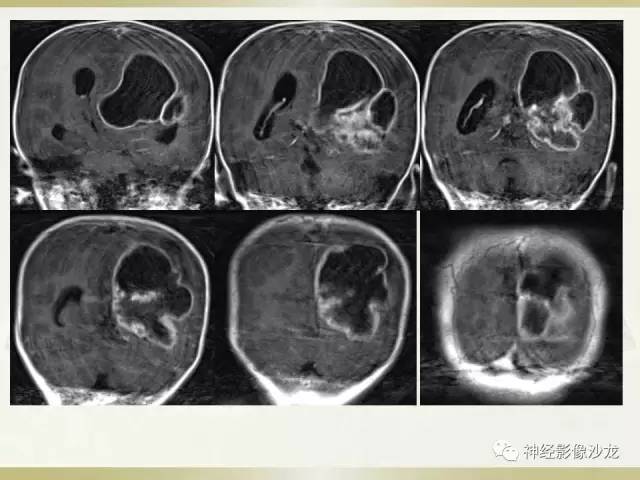

【病例】幕上脑实质内室管膜瘤1例CT及MR影像讨论

囊实性占位,有钙化,实性成分明显强化

主体在脑内,还是定位脑内吧

应该是脑内

侧脑室三角区受压

水肿不够,钙化交成熟

室管膜瘤

影像挺符合

儿童,侧脑室三角区旁、囊变、钙化、出血,下次见到首先考虑啊